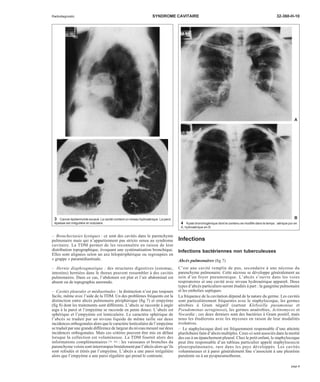

10 Embolies septiques.

A. Nodules multiples à contours mal définis.

B. En tomodensitométrie, ces nodules sont périphériques et excavés.

A

B

11 Staphylococcie pleuropulmonaire.

A. Pneumatocèle.

B. Un an plus tard, la radiographie thoracique est normale.